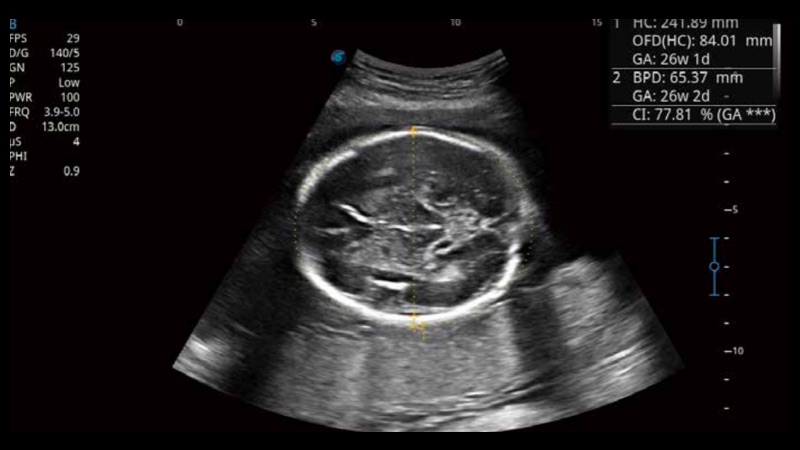

S-Fetus基于大數(shù)據(jù)深度學習算法,能夠幫助您在產(chǎn)前篩查過程中智能識別胎兒標準切面、自動測量并錄入報告。一個按鍵,即可智能、精準、高效地獲取胎兒生理指標,極大簡化您的產(chǎn)科檢查操作。

可快速對產(chǎn)科掃查切面完成胎兒生理學參數(shù)的自動測量,減少操作者按鍵次數(shù),大幅提升檢查效率。